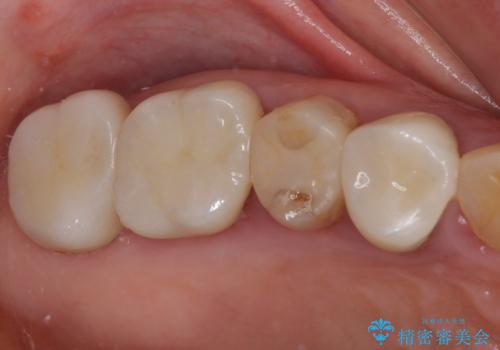

全ての奥歯の銀歯をセラミックに メタルフリー治療

途中体調を崩されてしまい、その間に仮歯が外れてしまうなど、治療期間が長引いてしまいました。

治療期間はかかってしまいましたが、念願のメタルフリーとなり、患者様には大変満足していただきました。